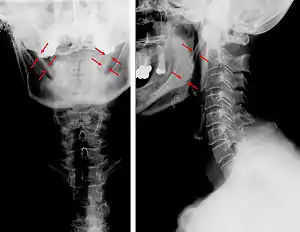

| Anteroposterior and lateral radiographs of cervical spine showing ossification of the stylohyoid ligament on both sides | |

CT scan, coronal section showing bilateral extended styloid process and stylohyoid ligament ossification (incidental finding)

Imaging is important and is diagnostic. Visualizing the styloid process on a CT scan with 3D reconstruction is the suggested imaging technique.[11] The enlarged styloid may be visible on an orthopantogram or a lateral soft tissue X ray of the neck.